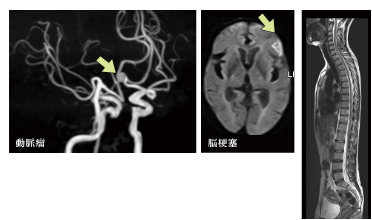

脳ドックの必要性

脳卒中や認知症の予防に

脳卒中も認知症も予防が最も重要です。高血圧がある方は、脳動脈瘤の破裂によるくも膜下出血、脳出血、脳梗塞が生じやすいと言われていますが、高血圧や糖尿病によって認知症の危険性も2倍ほど高くなります。悪玉コレステロールによる動脈硬化を予防、早期発見することはもちろんですが、心房細動という危険な不整脈を見つけ出すことで重症な脳梗塞を避けることができます。

脳卒中

脳卒中は強い後遺症が残ることから要介護の最大の原因です。また、日本で3番目に多い死因で、国民病と言われています。しかしながら、脳卒中は突然発症するまでは症状が出ないことが多く、脳MRIやMRAで脳や脳血管の状態をあらかじめ把握してリスク管理をすることが重要です。